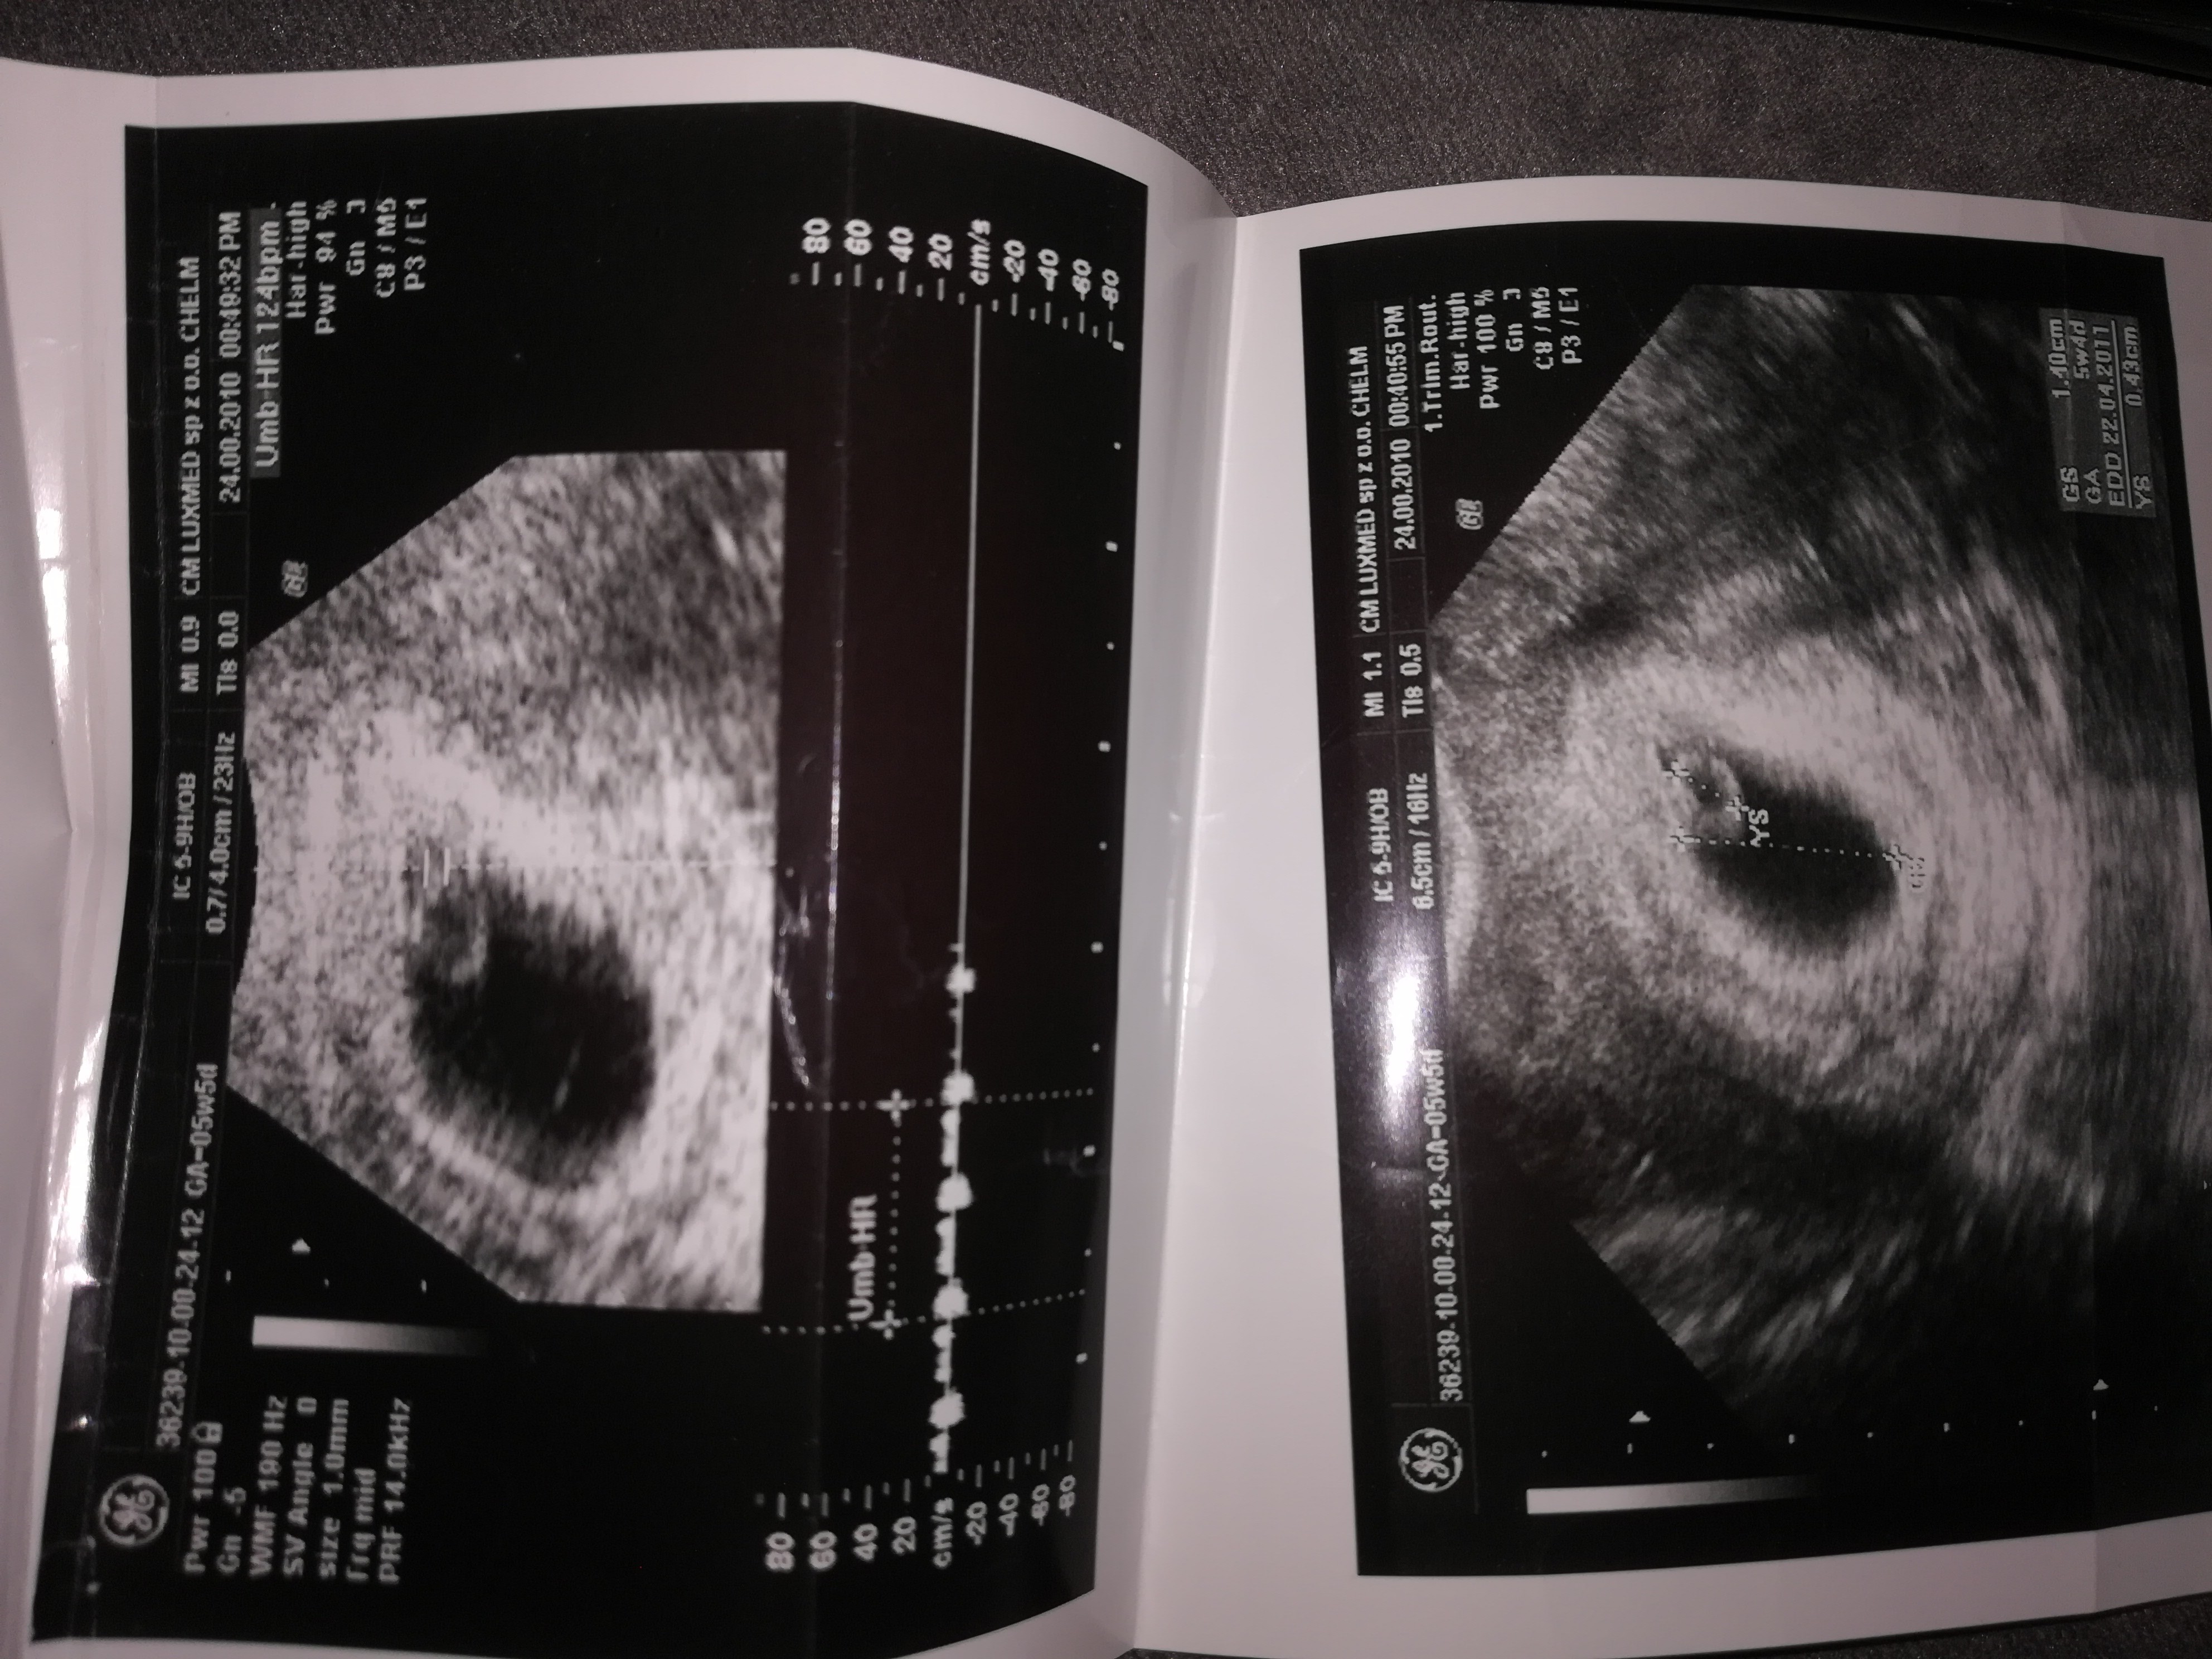

I w tym 5 tydzień 5 dzień mam zaznaczone że biło serduszko dlatego byłam zdziwiona jak poszłam na usg że nie było widać zarodka tylko pecherzyk.

Zobaczcie to usg córki z 5 tygodnia i 12 tygodnia i w tym 5 mam serduszko zaznaczone